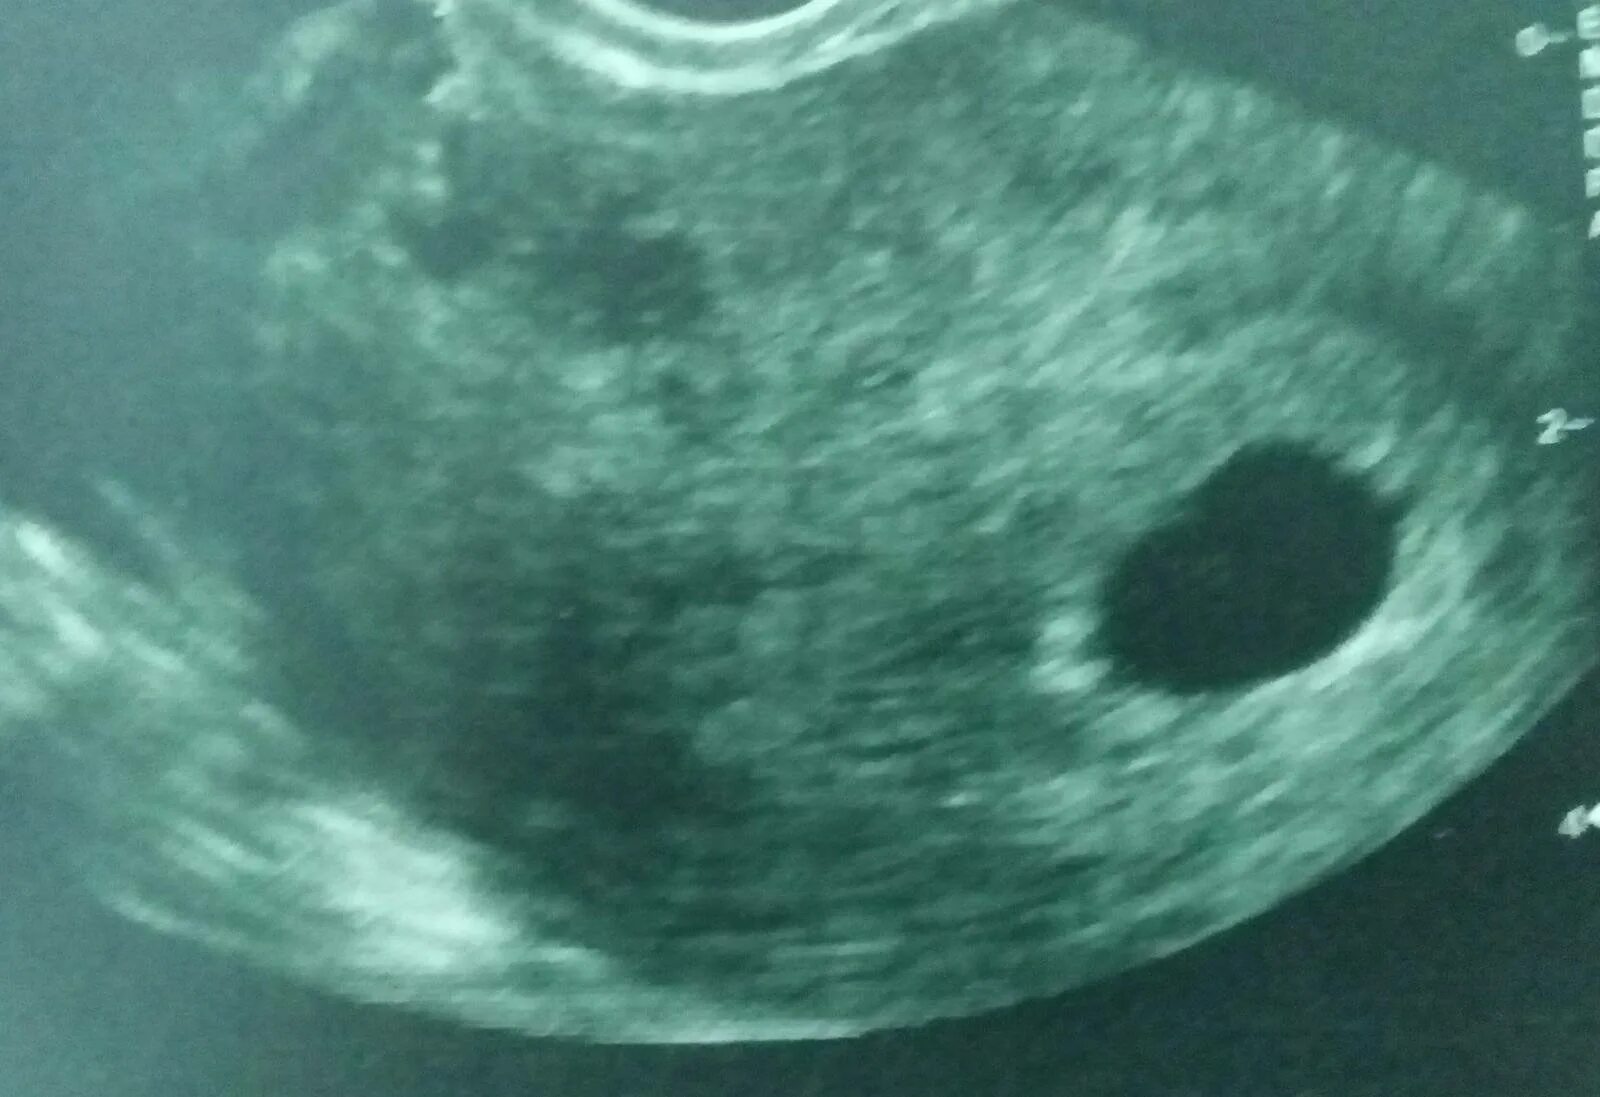

Плодном яйце не визуализируется эмбрион